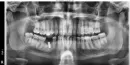

Это нарушение технологии, налицо по снимку явления периимплантита, одной из причин которого могло явиться отсутствие нагрузки на кость.